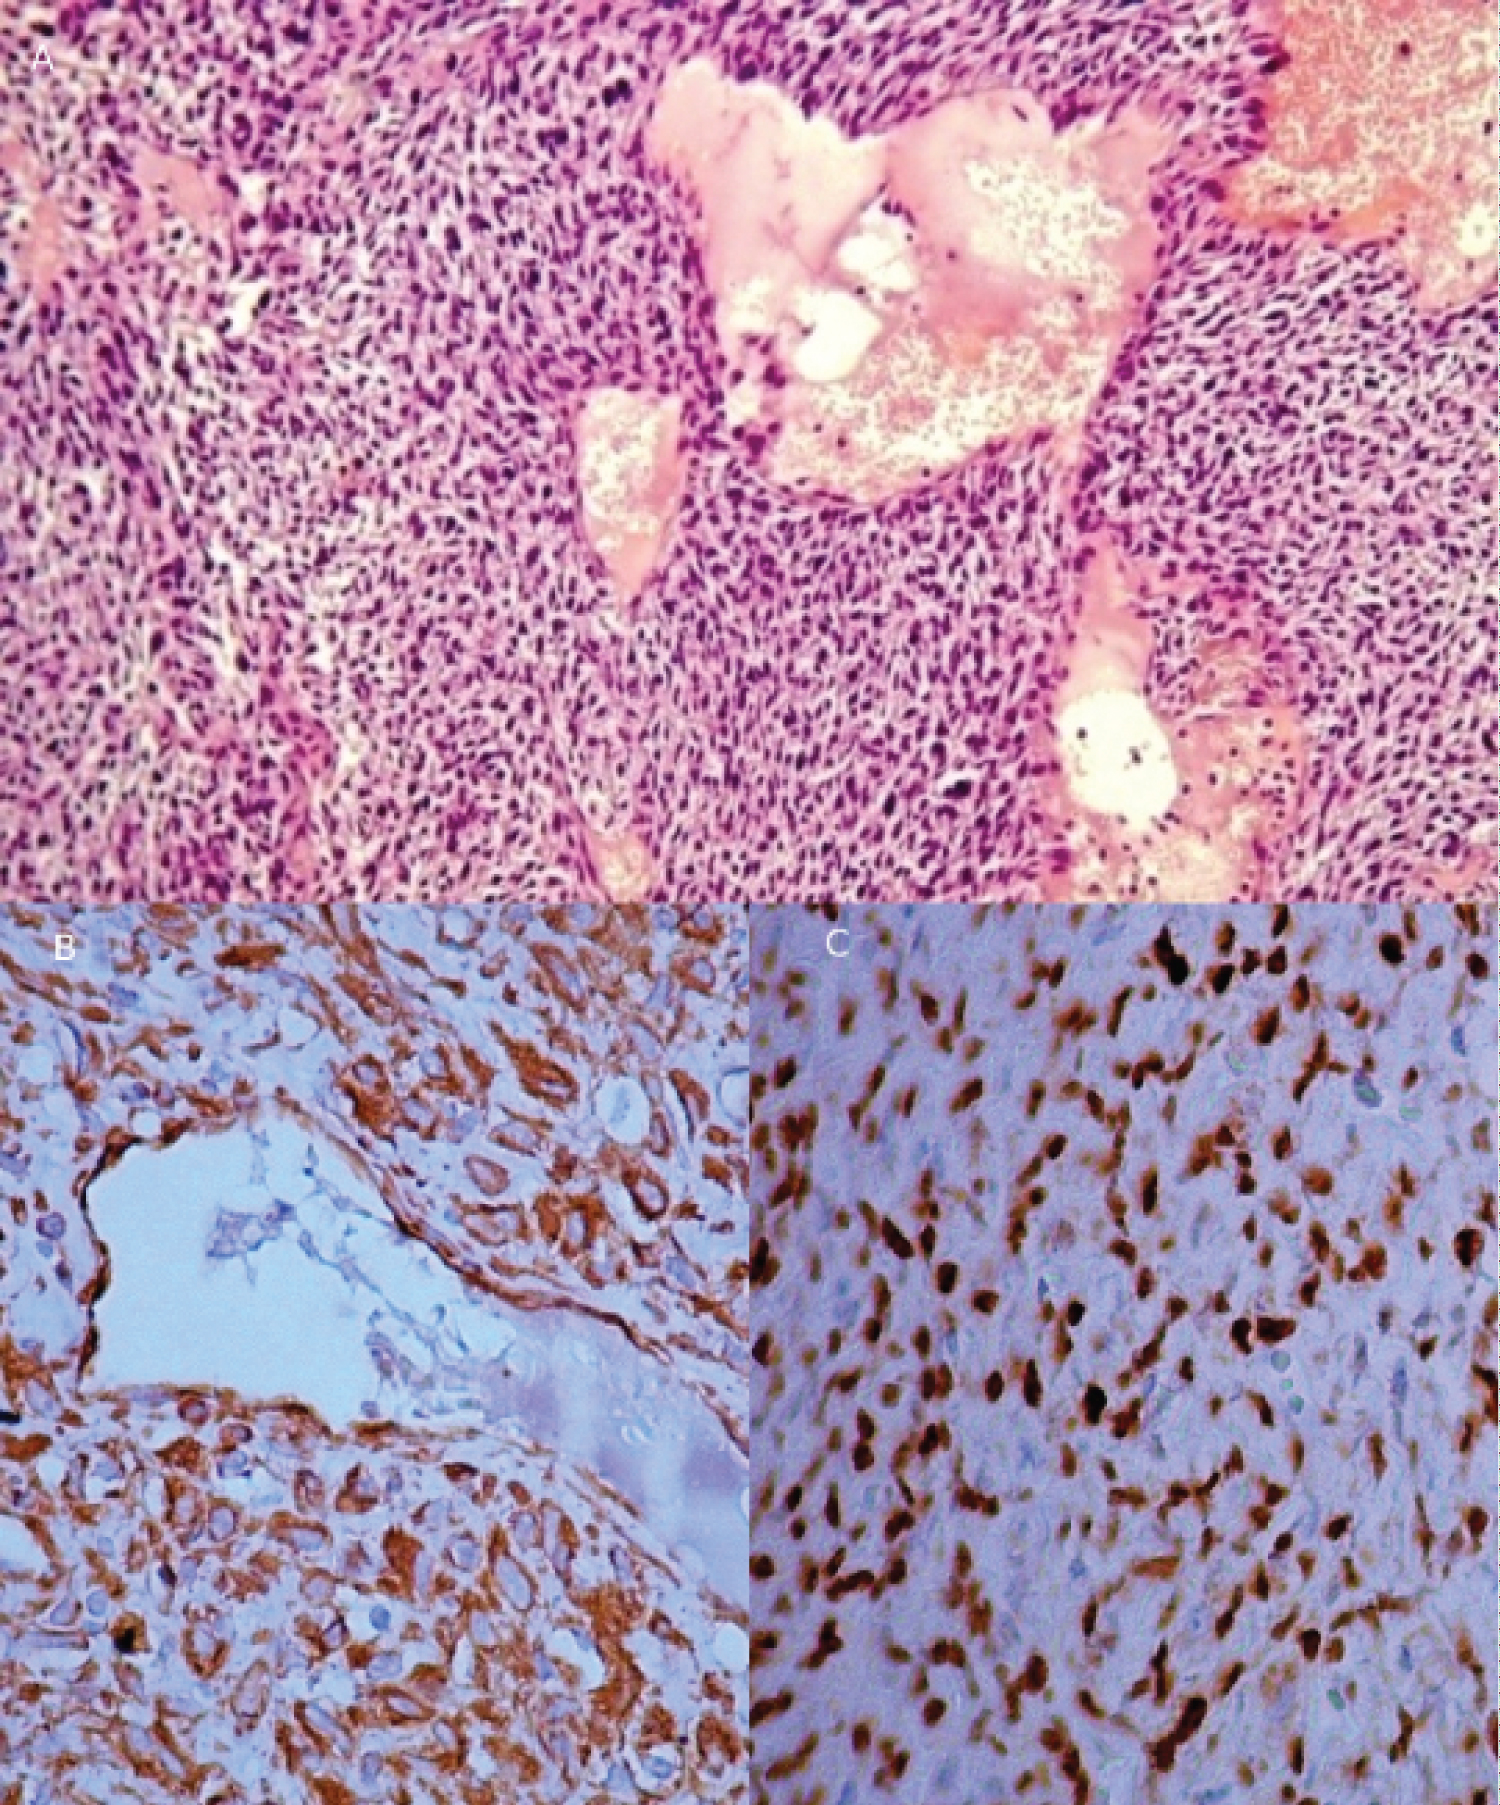

Tumor tissue was represented by rather dense sprawls rounded, oval, less often spindle-shaped cells, with dark hyperchromic cores. The cytoplasm was eosinophilic, and nuclei contained signs of pathological mitosis. There were numerous sinusoidal slits, capillaries, vessels, and vascular slits like "staghorn" lined with endothelium between cells. Large-scale hemorrhages and foci of necrosis were also seen (Figure 3A).

For differential diagnosis with anaplastic meningioma, the immunohistochemical study was conducted on a standard protocol, using the company's visualization system «Dako». Tumor cells were diffusely positive for STAT6 and vimentin, focal-positive to CD34 (Figure 3B and Figure 3C), and negative for EMA and progesterone. The index of proliferative activity Ki67 was not more than 10%.

Figure 3: A) Solitary fibrous tumor/haemangiopericytoma, WHO grade II; B) The positive reaction of tumor cells to CD34; C) Nuclear localization of STAT6 protein. View Figure 3

Based on pathohistological and immunohistochemical studies of solitary fibrous tumor/haemangiopericytoma diagnosis, WHO grade II, ICD-O code 8815/3 was established.